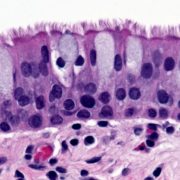

Our lungs are constantly bombarded by inhaled pathogens, allergens, toxins and debris. The airway epithelium is the first line of defense against these contaminants. It accomplishes this by acting as a selective physical barrier, by participating in immune surveillance and response, and by the directional movement of cilia that sweep contaminants adhered to the mucus layer out of the lungs. Epithelial dysfunction underlies disease phenotypes and promotes disease progression in chronic inflammatory airway conditions like cystic fibrosis, asthma and COPD – however, current treatments do not directly target or reverse dysfunction. Our work focuses on the multiciliated cells, which each contain hundreds of motile cilia. We use mice and primary mouse and human cell culture to study how multiciliated cells adopt their cell fate, build cilia and orient the cilia for directional clearance. We investigate the pathways that drive these processes during normal development and regeneration and study how they are misregulated in human disease. Our research has the potential to develop novel biomarkers and therapeutics for individuals suffering from chronic airway diseases.